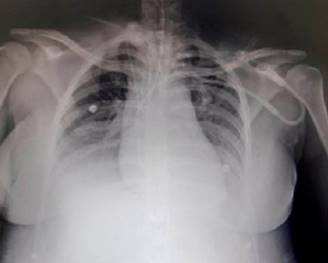

Al momento de su ingreso a unidad de cuidados intensivos (UCI), se encuentra a la exploración física con tensión arterial de 100/52 mmHg, presión arterial media de 68 mmHg, frecuencia cardiaca 91 lpm y temperatura de 37 grados, bajo efectos de sedación con propofol, RASS-5 (por sus siglas en inglés Richmond Agitation-Sedation Scale), intubación orotraqueal conectada a ventilador mecánico en modalidad control volumen, con volumen tidal 375 mL, PEEEP (por sus siglas en inglés positive end-expiratory pressure) 5, cmH2O, FiO2 40%, reporte de gasometría arterial pH 7.20, PaCO2 40 mmHg, PaO2 83 mmHg, HCO3 15.7, DB -12.5, con saturación periférica 96%, hemodinámicamente sin requerimientos de vasopresor, en anuria. Se objetivó en la analítica clínica deterioro de la función renal con incremento en las cifras de azoados, aumento de transaminasas, bilirrubina: deshidrogenasa láctica (DHL) y elevación importante de ácido úrico, así como anemia, trombocitopenia e incremento en el conteo leucocitario: urea 140 mg/dL, creatinina 7.34 mg/dL, ácido úrico 8.5 mg/dL, los electrolitos reportaron Na 136 mEq/L, K 6.8 mEq/L, CL 106 mEq/L, P 11.7 mEq/l, Mg 5.3 mEq/L, Ca 7.28 mEq/L, las pruebas de función hepática reportaron aspartato aminotransferasa 32 UI/L, alanina aminotransferasa 64 UI/L, fosfatasa alcalina 78 UI/L, DHL 3575 UI/L, bilirrubina total 0.24 mL/dL, en lo hematológico con presencia de gingivorragia y hematomas en extremidades, reporte de laboratorio con Hb 7.5 g/dL, hematócrito (HTO) 22.7, plaquetas 17, 000, leucocitos 36, 410, tiempo de protrombina (TP) 13.7, tiempo parcial de tromboplastina (TPT) 29.5, INR 1.21. Se calculó un SOFA score a su ingreso de 11 puntos con mortalidad de 50%. Se inició tratamiento de reanimación con líquidos para optimizar la función renal sin mejoría, considerándose candidata para terapia de reemplazo renal. Se realiza transfusión una aféresis plaquetaria, colocación de catéter de hemodiálisis e inicio de terapia de reemplazo renal lenta continua (TRRLC) mediante hemodiafiltración venovenosa continua (HDFVVC). La radiografía anteroposterior de tórax mostró tejidos blandos de adecuada densidad, estructuras óseas de densidad normal, parénquima pulmonar normal con presencia de derrame pleural bilateral (Figura 1).